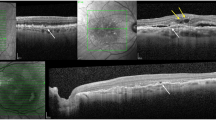

By in vivo OCT, progressive resolution of the haemorrhage and gradual transformation of sub-RPE fluid to fibrous hyperreflective tissue, progressive macular atrophy, and variation in external limiting membrane (ELM) visibility were observed. Histology showed intense photoreceptor loss with preservation and self-adhesion of macular Müller glia resulting in ELM condensation. The comparator eye exhibited shed cone inner segments among subretinal erythrocytes.

This is the most detailed clinicopathologic correlation of nAMD with SMH resolution to date, and the first in the OCT era. Our results reveal profound macular neurodegeneration and gliosis, signified by condensed ELM, soon after haemorrhage begins. Intensified OCT reflectivity of the ELM, an important retinal barrier, has potential as a biomarker for severe photoreceptor loss and gliosis.